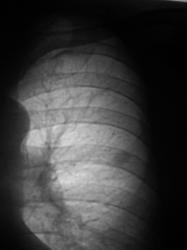

Окружающая легочная ткань - 2008 и 2009 г.

Вердикт диспансера - "наблюдение в динамике".

В Мособлонкодиспансере то же самое . Помнится, один дедок мне выговаривал: "Из-за вас я время потерял (делал для устройства на работу), деньги (на проезд, в маршрутке льготы не действуют), перенервничал, а ничего не подтвердилось..." Подтвердилось через 2 года, когда диагноз можно было глядя на больного, а не на рентгенограммы.